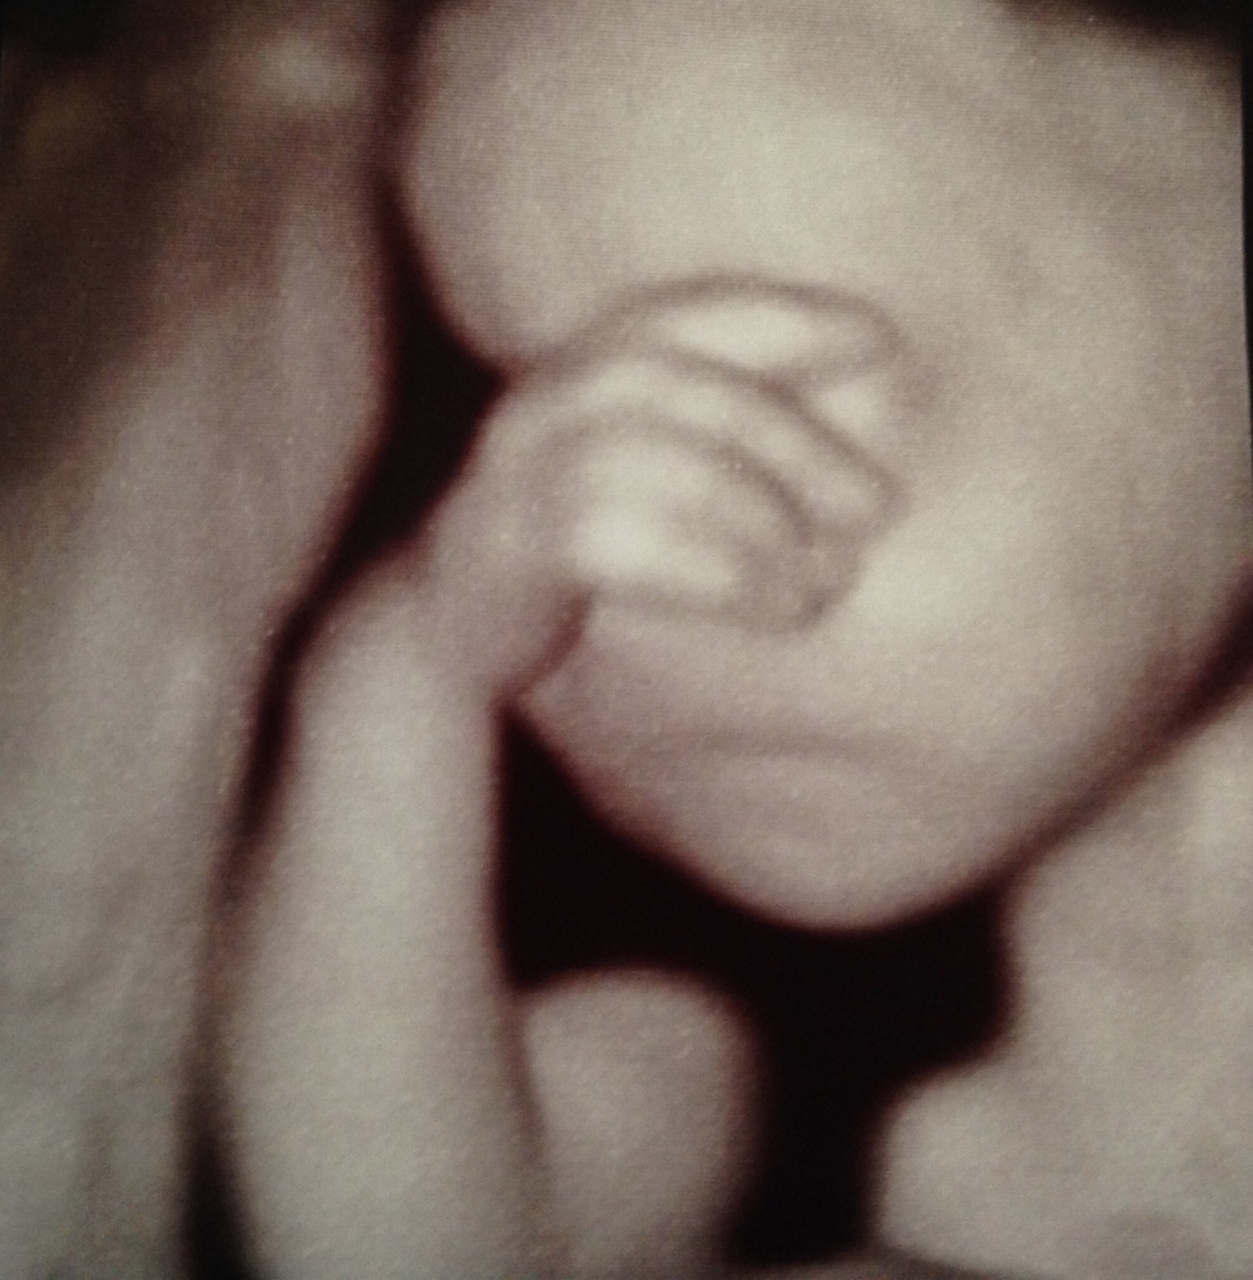

(and yes, these are actual 3D ultrasound pictures of Ella – she looks great already!)

Awesome! I love the shot of her covering her eyes as if to say, “I can’t even HANDLE this.”

RIGHT?! that’s my favorite, too. :)

Yes! And we think she has Bart’s “pointier” nose and my connected earlobes ;) Oh, modern technology.